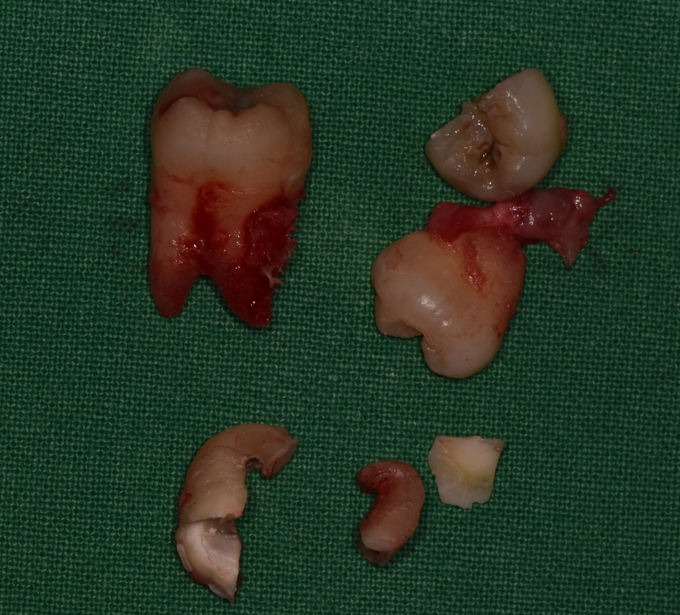

개수도 많기도 하고, 환자분이 시술 중 통증도 느끼고 싶지 않으셔서

의식하진정마취(수면마취)로 발치를 진행하였고, 통증 없이 치료를 마치셔서 만족하셨습니다.